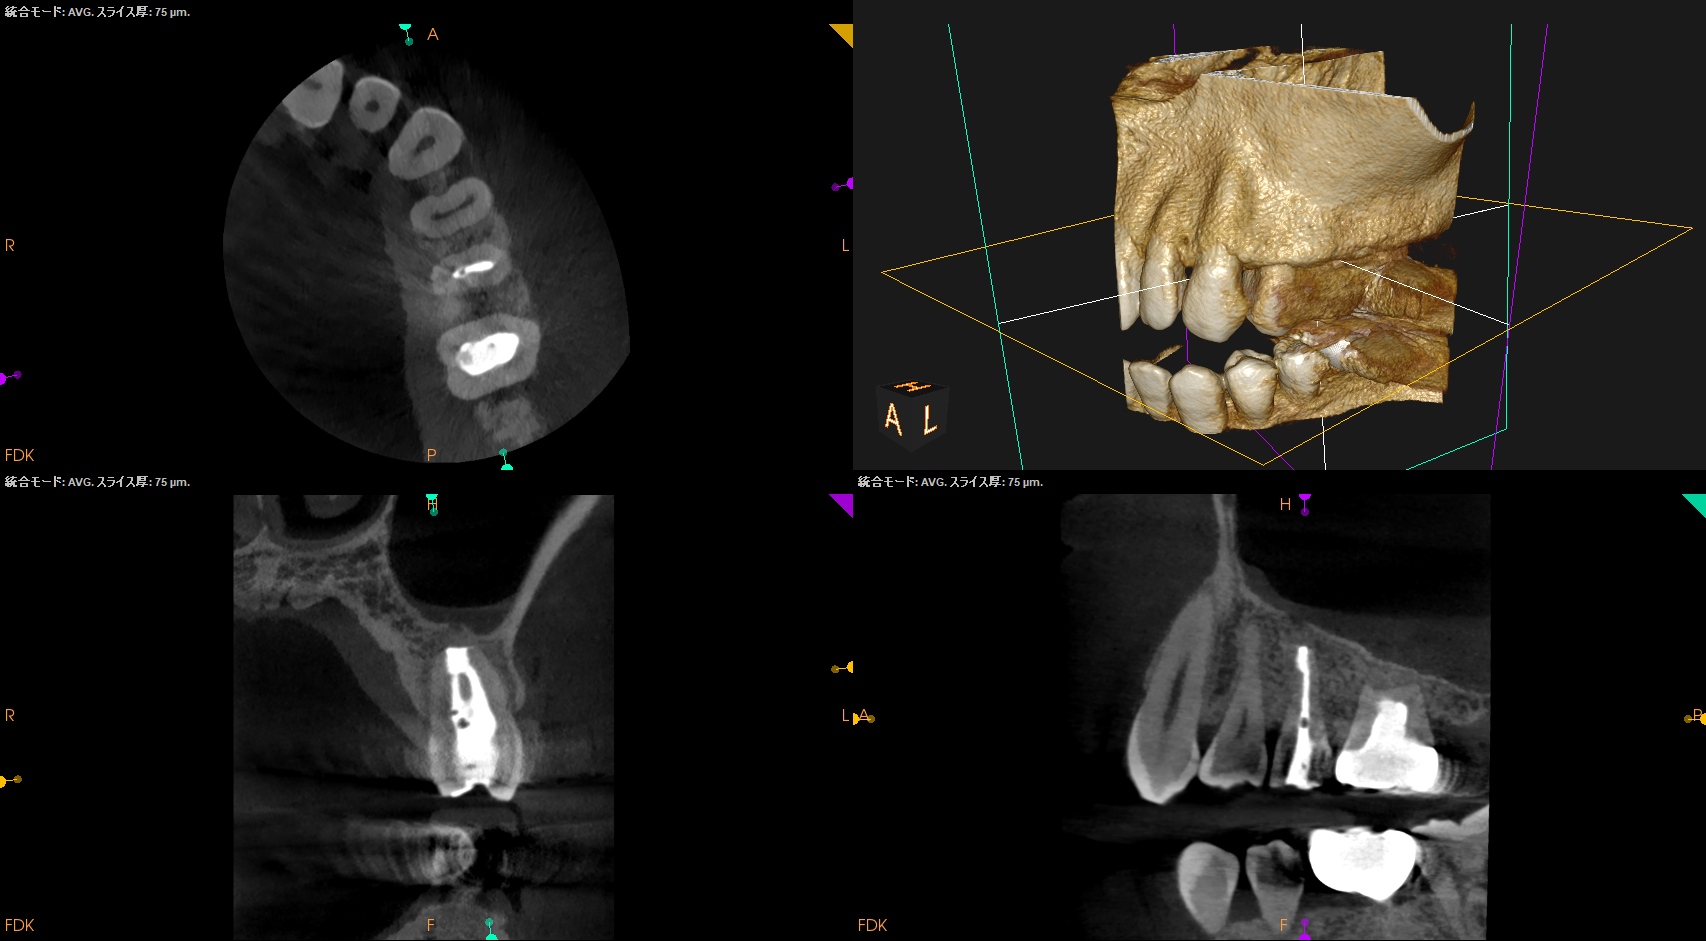

#13 Intentional Replantation 1yr recall(2026.4.10)

1年前と比較した。

歯槽骨の欠損部分は完治した。

打診時のアンキローシス音もない。

ということで、臨床症状もないのでこの日で終診とさせていただいた。